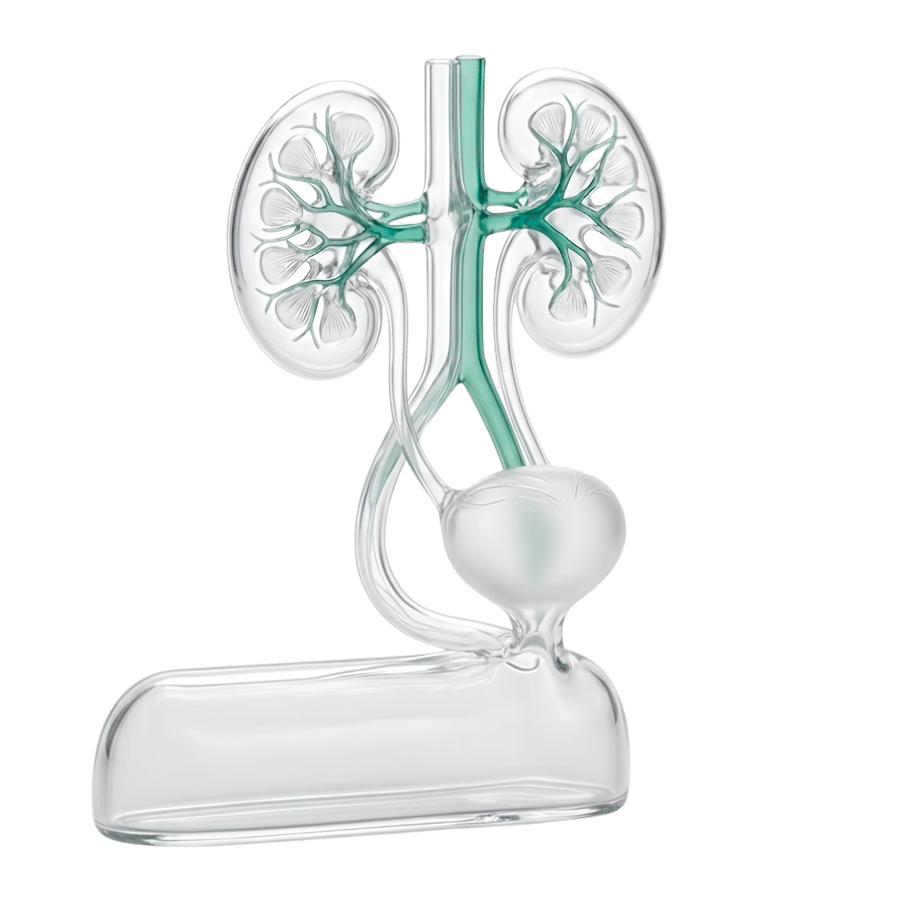

Урология / Андрология

қызметтер: 6